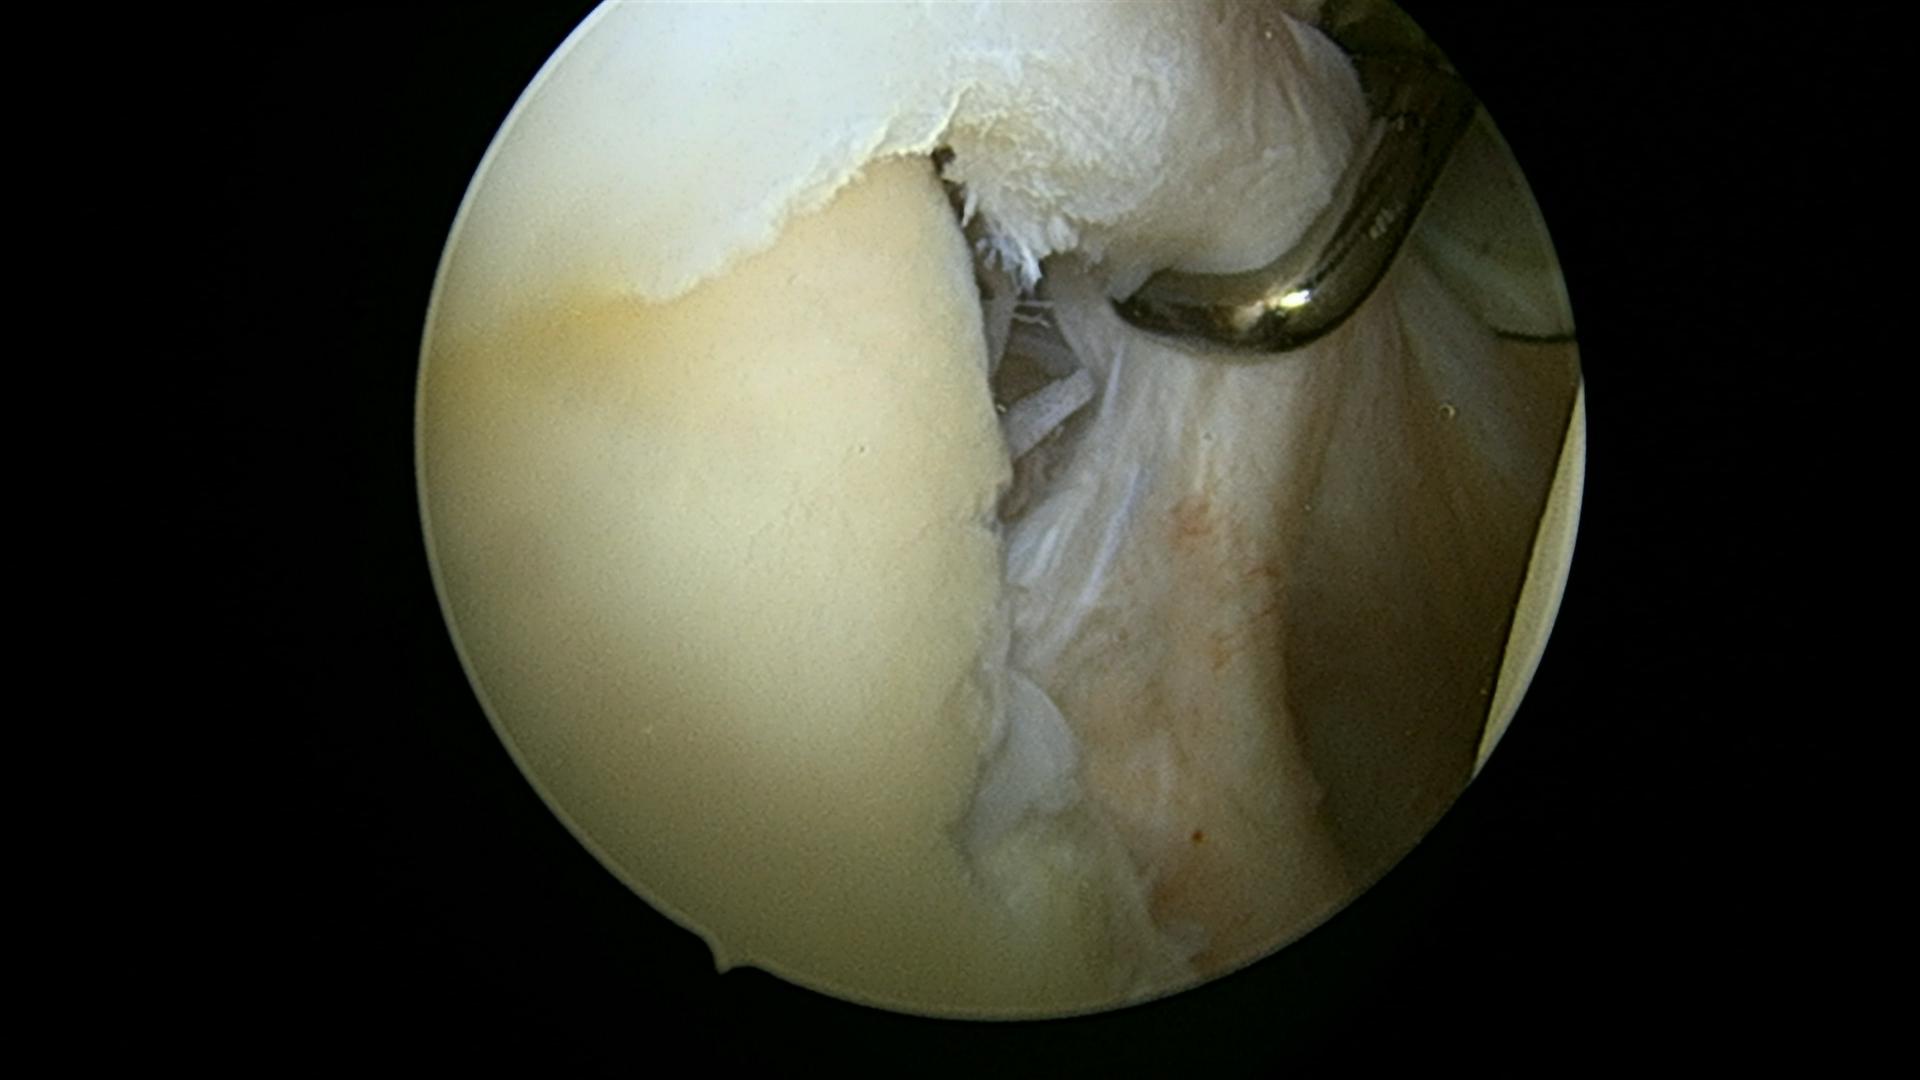

Bankart læsion, før: